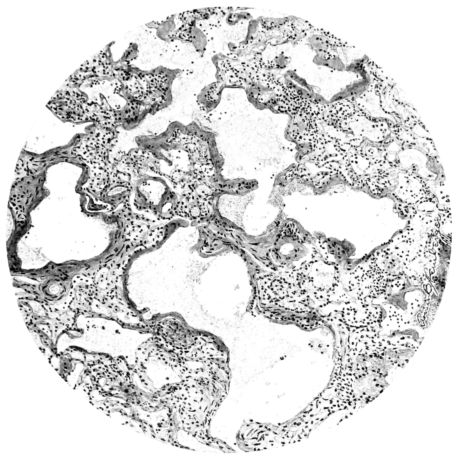

FIG. II. AUTOPSY NO. 98. DRAWING OF A SECTION THROUGH A TRACHEA SHOWING NECROTIZING HEMORRHAGIC INFLAMMATORY PROCESS OF THE MUCOSA.

The changes are less marked, perhaps, in the trachea than in its finer ramifications. The mucosa is constantly more or less destroyed and large areas, usually focal, are entirely devoid of their epithelial covering. This is replaced by a sparse exudate, composed largely of red blood cells, mucus, a small amount of fibrin, and nuclear fragments (Fig. II). It may dip into the submucosa for a short distance, but usually these indentures are associated with the ducts of the mucous glands into which the inflammatory reaction extends. A more striking feature than the exudate, however, is the edema and the congestion of the submucosa. The loose areolar tissue of the submucosa is spread widely apart, and throughout it distended blood vessels are very conspicuous. Occasionally such a vessel is broken and actual hemorrhage appears in the submucosa. Occasionally, too, the inflammation extends down the duct to the mucous gland itself, and here, also, aplastic inflammatory reaction is evident, inasmuch as the acini now stain intensely red with the cells undifferentiated from each other and specked here and there by broken remains of the dead nuclei (Fig. III). After the disease has continued for a short period, even at the end of five or six days, some regeneration of the epithelial lining may be seen (3) (Fig. IV). But despite this, the acute picture persists, and there goes on, side by side, an attempted repair characterized by epithelial regeneration and the same evidence of acute change. Since the lesion is essentially a superficial one, scars or contractures of any extent are not encountered in the trachea, even in examples of the disease that have ended fatally only after many weeks.[4]